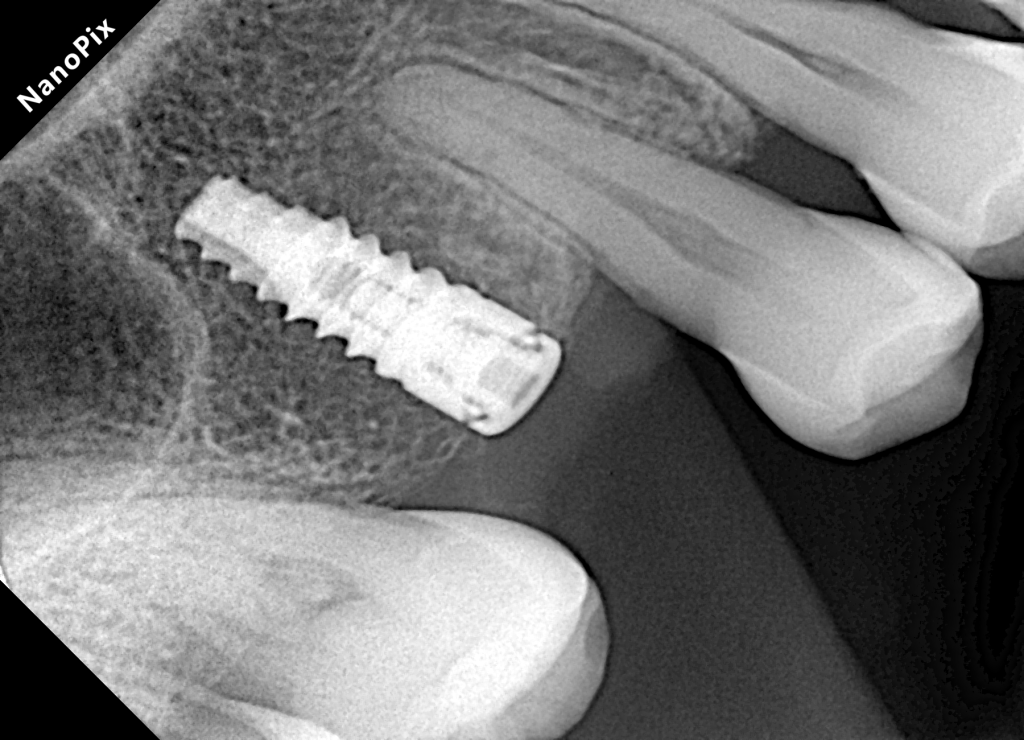

Implantes Dentales

Los implantes dentales son una solución de vanguardia para reemplazar dientes perdidos. Consisten en pequeñas raíces artificiales hechas de titanio, que se colocan en el hueso maxilar o mandibular para proporcionar una base sólida para un diente artificial (corona) o incluso un conjunto completo de dientes. Utilizamos los mejores implantes del mercado europeo Sweden & Martina.